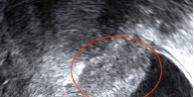

Patiente de 35 ans sans enfant et sans antécédent particulier.

Elle n’a pas de contraception. Elle consulte pour dysménorrhée, algies diffuses, dyspareunie progressive, et dysurie menstruelle d’apparition récente.

L’examen clinique retrouve une masse annexielle droite, vraisemblablement ovarienne et une sensibilité pelvienne générale.

Une échographie est demandée. Voici les résultats avec une vue de l’utérus, une vue de l’annexe droite et une au niveau de la vessie.